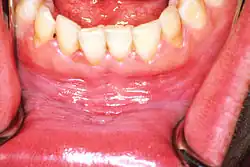

Leukoplakia in the lower labial sulcus

Homogeneous leukoplakia in the floor of the mouth in a smoker. Biopsy showed hyperkeratosis

Sometimes leukoplakia of the floor of mouth or under the tongue is called sublingual keratosis,.[19] though this is not universally accepted to be a distinct clinical entity from idiopathic leukoplakia generally,[19] as it is distinguished from the latter by location only.[3] Usually sublingual keratoses are bilateral and possess a parallel-corrugated, wrinkled surface texture described as "ebbing tide".[3]